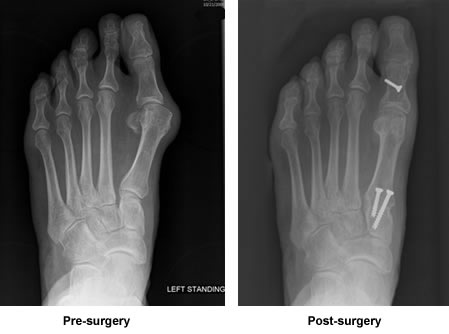

My foot is no longer something I want to hide because of the "walnut" on the side of my toe. Shoes fit easily, sandals look great, and the pain is gone.